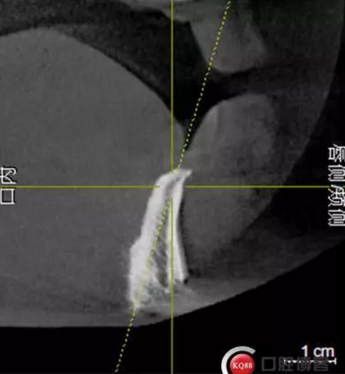

檢查:上頜無(wú)牙頜假牙穩(wěn)定性尚可,下頜3435364243殘根;33殘冠1-2度松動(dòng),其他牙齒缺失;CBCT檢查:下頜牙槽骨前牙區(qū)骨高度足,后牙區(qū)骨高度最低為8mm,骨寬度足。

1)術(shù)前檢查,拍攝臨床照片及CBCT檢查,制取活動(dòng)義齒參考模型,指導(dǎo)后期最終修復(fù)的牙齒排列

2)術(shù)前準(zhǔn)備及手術(shù)過(guò)程,測(cè)量血壓及血糖,簽種植知情同意書;嚴(yán)格遵循無(wú)菌操作,局麻下采用微創(chuàng)技術(shù)于323436分別植入osstem4.0X10,4.0X10,4.5X7; 434446分別植入osstem4.0X1O,4.0X10,4.5X7.初期穩(wěn)定性均達(dá)到了35N.CM以上;嚴(yán)密縫合,止血,種植體位點(diǎn)和方向與設(shè)計(jì)一致。